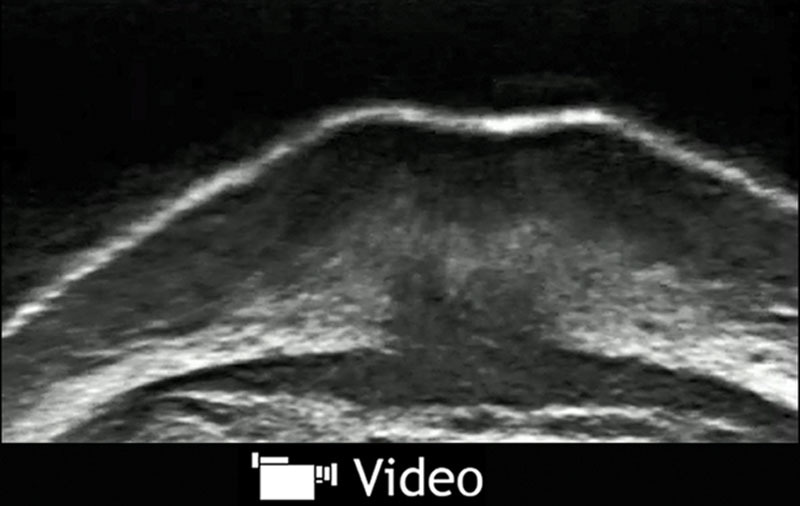

The bundles of the crossing fibers of the OOM and the morphological changes of the philtrum were clearly visualized without pressure to the philtrum skin (Fig. 1). During lip protrusion, the OOM was observed to spread from both sides into trumpet-like shapes crossing the midline of the contralateral lip skin, which extends to approximately 7–10 mm outside the philtrum ridge. The skin was pulled most tightly inward at the outer end of the insertions. Although muscle fibers were not inserted into the skin at the philtrum hollow, there was a marked increase in the thickness of the muscle and the subcutaneous tissue. The thickening of the deep muscle fibers, which are regarded as muscle crossing between both of the modioli, could not be confirmed (see video, Supplemental Digital Content 1, which demonstrates lip protrusion, http://links.lww.com/PRSGO/A438).

Fig. 1.

A, Resting. B, Lip protrusion. CF, crossing fiber; DCT, deep connective tissue; Epi, epithelium; LCT, loose connective tissue; PhR, philtrum ridge.

Video Graphic 1.

. See video, Supplemental Digital Content 1, which demonstrates lip protrusion, http://links.lww.com/PRSGO/A438.